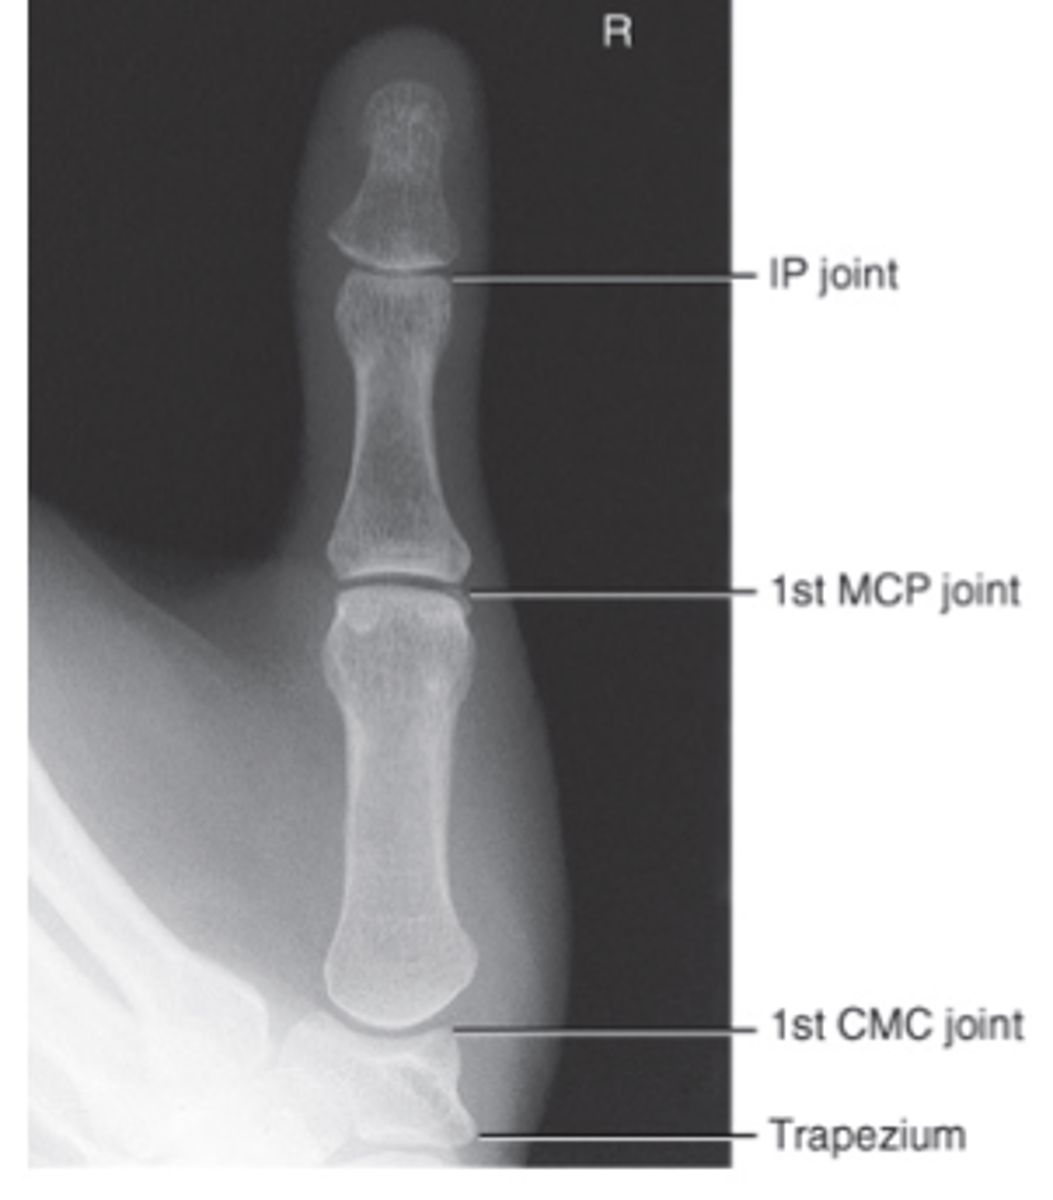

Lateral Thumb